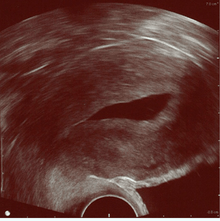

![]() Left hydrosalpinx on gyn. ultrasonography | |